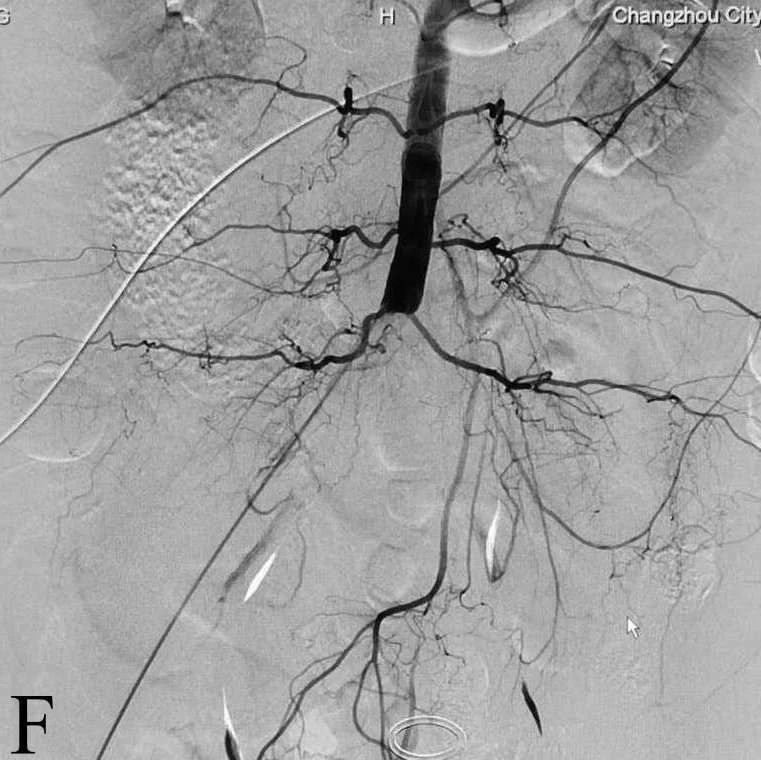

F:腹主动脉下段急性闭塞